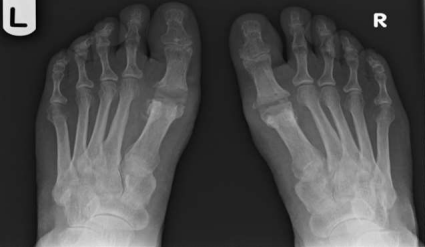

Figure 1

Figure 2

Figure 3

Radiographic evaluation revealed a preoperative mean hallux valgus angle (HVA) of 32.6 degrees (SD = 5.4) and an intermetatarsal angle (IMA) of 14.2 degrees (SD = 3.1), indicating significant deformity and joint involvement. Following the silastic joint replacement arthroplasty, there was a significant improvement in the radiographic measurements. The postoperative mean HVA decreased to 12.8 degrees (SD = 3.6), and the mean IMA decreased to 5.1 degrees (SD = 2.2). These changes were statistically significant (p < 0.001), indicating successful correction of the deformity.